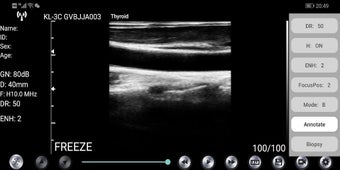

WirelessKUS es una aplicación gratuita de transductor de ultrasonido médico desarrollada por kontedmed para dispositivos Android. Permite al usuario establecer una conexión inalámbrica entre el transductor de ultrasonido y su teléfono inteligente o tableta a través de WiFi. La aplicación ofrece una variedad de funciones como gestión de información del paciente, ajuste de ganancia, control de profundidad, ajuste de frecuencia, ajuste de rango dinámico, control de área de imagen, estado de congelación/en vivo, botón de ajuste de ganancia, herramientas de medición, opciones de guardado de imágenes y videos, selección de canal de WIFI, guía de punción, agregado de comentarios, selección de modelo de imagen, ajuste de posición de enfoque, ENH mejora, THI encendido/apagado y control de rango dinámico.

Para conectar el transductor de ultrasonido con la aplicación, el usuario debe ingresar la contraseña de WiFi por primera vez, que es el número de serie de la sonda en letras minúsculas. Después de la conexión de primera vez, la aplicación se conectará automáticamente con el WiFi de la sonda. La interfaz del software muestra el estado de la sonda y el usuario puede ajustar la configuración utilizando las diversas opciones disponibles. La aplicación también permite al usuario ajustar finamente la ubicación del punto de medición y eliminar todos los resultados de medición con un solo clic.